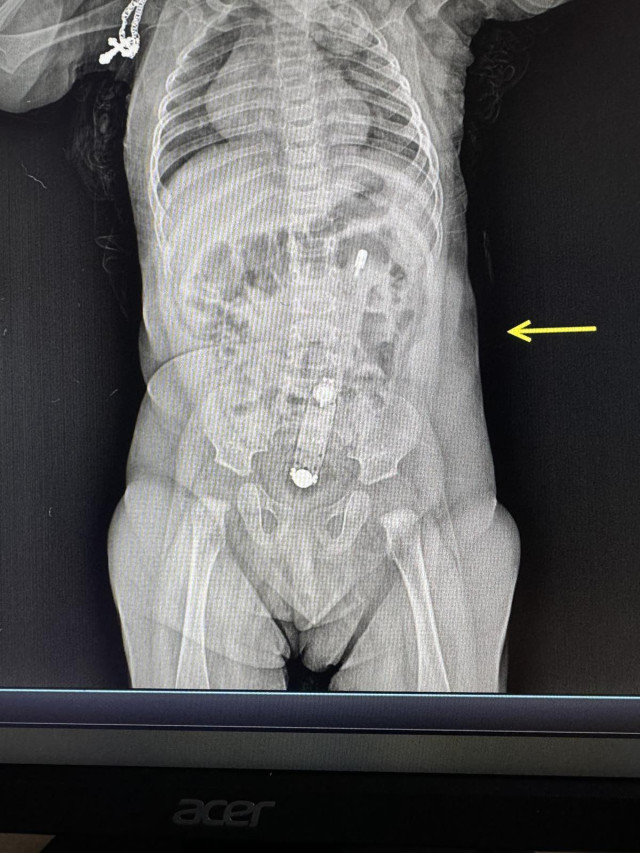

«На рентгені було чітко видно термометр, також він пальпувався через живіт. Дістати прилад було дуже непросто. Зробили це ендоскопічно, діяти треба було дуже обережно, щоб не травмувати немовляті анус та внутрішні органи. Самостійно градусник вийти не міг, натомість міг перфорувати кишківник або надалі спровокувати кишкову непрохідність», – розповідає хірургиня та ендоскопістка Волинська обласна дитяча клінічна лікарня Юлія Артишук.

«На рентгені було чітко видно термометр, також він пальпувався через живіт. Дістати прилад було дуже непросто. Зробили це ендоскопічно, діяти треба було дуже обережно, щоб не травмувати немовляті анус та внутрішні органи. Самостійно градусник вийти не міг, натомість міг перфорувати кишківник або надалі спровокувати кишкову непрохідність», – розповідає хірургиня та ендоскопістка Волинська обласна дитяча клінічна лікарня Юлія Артишук.